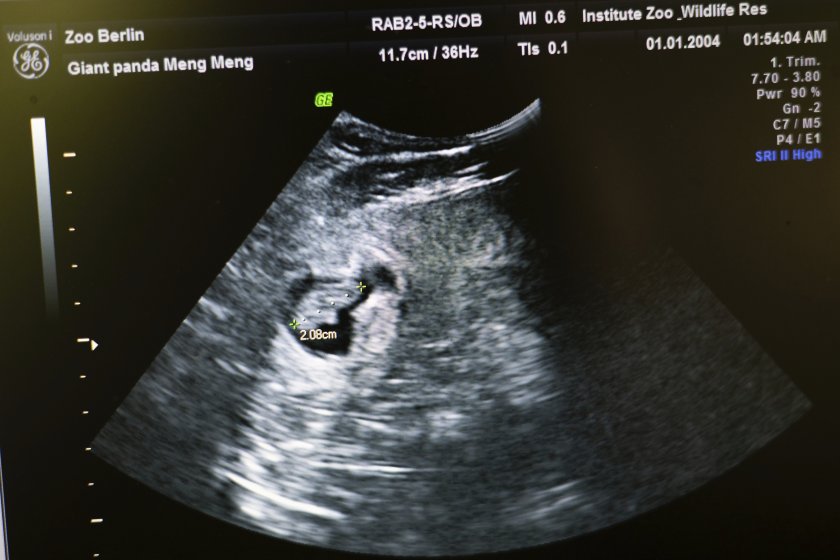

Женската огромна панда Мън Мън от зоопарка в Берлин чака близнаци, разкри ултразвуково проучване, предава Асошиейтед прес.

„ Първоначално можеше да се чуе един сърдечен удар, а малко по-късно и втори “, оповестиха от зоологическата градина.

Женската панда Мън Мън за последно роди близнаци през 2019 година, само че те бяха изпратени в Китай. Тя беше изкуствено оплодена през март тази година благодарение на интернационалните специалисти след интензивно наблюдаване и деликатна подготовка. Зоопаркът отбелязва, че женските панди са способни да се възпроизвеждат единствено към 72 часа годишно, отбелязва ДПА.